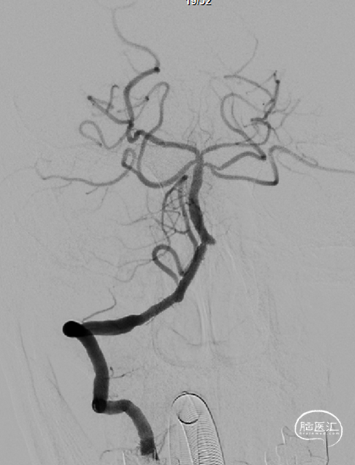

术后影像

术后即刻影像及患者术后情况:

造影见狭窄位置狭窄解除,支架贴壁良好,后循环各分支动脉显影良好。术后次日患者行走不稳情况明显改善,术后1月随访患者行走如常,未再发头晕。